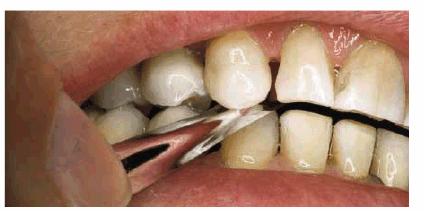

Figures 29-6A, 29-6B, 29-6C, 29-6D, and 29-6E illustrate a patient who did not care much about his

his smile improved. Figures 29-6A, and 29-6D show the worn and discolored central incisors and the

crowded lower anterior incisors. Figure 29-6B shows cosmetic contouring of the lower incisors.

Figures 29-6C, and 29-6E illustrate the completed esthetic improvement following

composite resin bonding of the central incisors.

Figure 29-6A: This 65-year-old man displayed worn, discolored maxillary central incisors with a fractured anterior composite restoration on tooth #9.

Figure 29-6B: Cosmetic contouring of mandibular incisors.

Figure 29-6C: The view after composite resin bonding of his central maxillary incisors.

Figure 29-6D: This man avoided smiling to hide his worn, discolored, and fractured central incisors.

Figure 29-6E: Note how much younger and happier the patient is following his esthetic dental treatment.